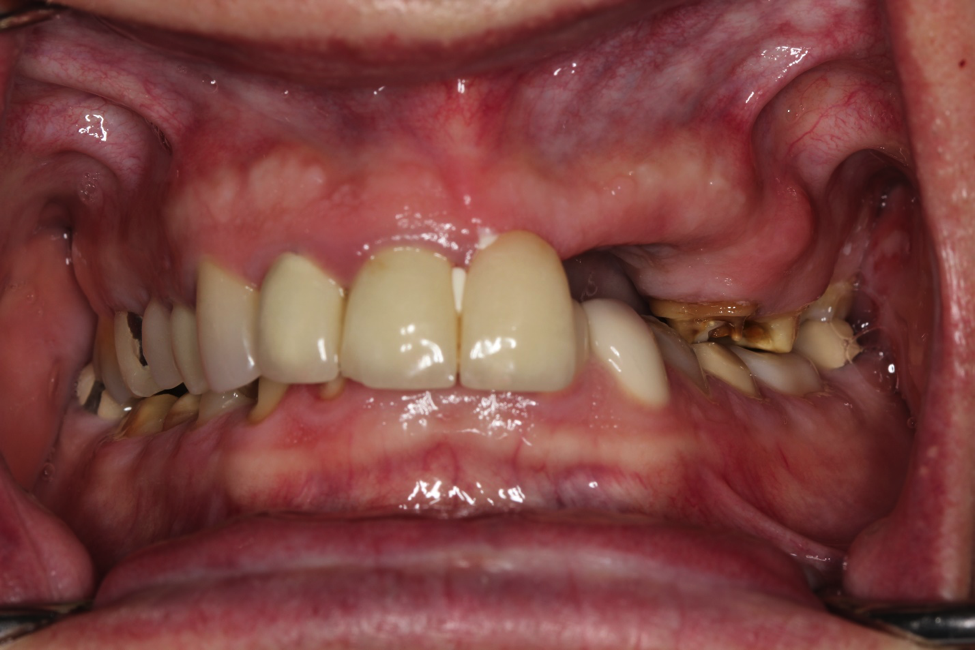

This patient came to us with several completely worn teeth. He also had some teeth missing. We had to do several things to ensure we could make him teeth that looked and felt normal. He had to undergo both periodontal surgery and implant surgery. We then restored his smile with crowns and implant crowns. He loves his new teeth.